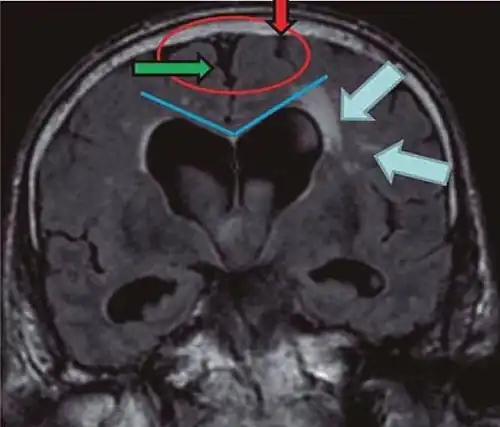

- Imaging from magnetic resonance imaging (MRI) or computed tomography (CT) is needed to demonstrate enlarged ventricles and no macroscopic obstruction to cerebrospinal fluid flow. Imaging should show an enlargement to at least one of the temporal horns of lateral ventricles, and impingement against the falx cerebri resulting in a callosal angle ≤ 90° on the coronal view, showing evidence of altered brain water content, or normal active flow (which is referred to as "flow void") at the cerebral aqueduct and fourth ventricle.

| Normal pressure hydrocephalus | Brain atrophy | |

|---|---|---|

| Preferable projection | Coronal plane at the level of the posterior commissure of the brain. | |

| Modality in this example | CT | MRI |

| CSF spaces over the convexity near the vertex (red ellipse |

Narrowed convexity ("tight convexity") as well as medial cisterns | Widened vertex (red arrow) and medial cisterns (green arrow) |

| Callosal angle (blue V) | Acute angle | Obtuse angle |

| Most likely cause of leucoaraiosis (periventricular signal alterations, blue arrows |

Transependymal cerebrospinal fluid diapedesis | Vascular encephalopathy, in this case suggested by unilateral occurrence |

MRI scans are the preferred imaging. The distinction between normal and enlarged ventricular size by cerebral atrophy is difficult to ascertain. Up to 80% of cases are unrecognized and untreated due to difficulty of diagnosis.[22] Imaging should also reveal the absence of any cerebral mass lesions or any signs of obstructions. Although all patients with NPH have enlarged ventricles, not all elderly patients with enlarged ventricles have primary NPH. Cerebral atrophy can cause enlarged ventricles, as well, and is referred to as hydrocephalus ex vacuo. For these reasons it's utmost important to note that Evan's index although commonly used in imaging is not very specific for NPH. One recent systematic review and meta-analysis suggests that callosal angle has high diagnostic performance and is commonly used together with Evan's index.[23]